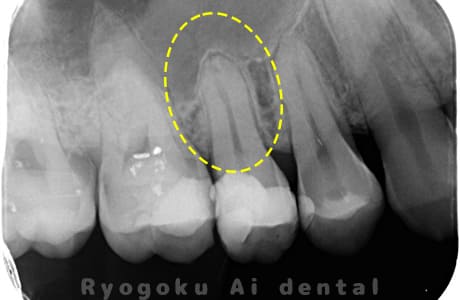

根管内の異物

- 原因

- 根管内異物(ファイル破折)による慢性根尖性歯周炎

- 治療期間

- 3ヶ月

- 治療内容

- マイクロスコープを使用した根管内異物除去並びにマイクロエンド

- 治療費用

- 121,000円(ファイル除去費用も込み)

他院で細い器具(ファイル)が根管内に破折した状態で、咬合痛を主訴に来院された患者様です。ファイルをマイクロスコープ下で除去し、根管治療を行ないました。